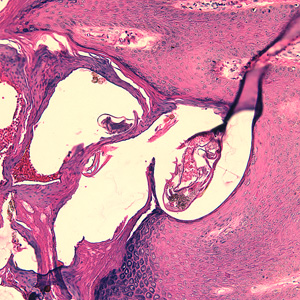

Case #244 – January, 2009

An 80-year-old resident of a long-term care facility presented with a skin condition manifesting as thick crusts over the skin accompanied by slight itching. The patient was originally treated for impetigo, with no resolution, and was ultimately admitted to the hospital for further testing. A skin biopsy was performed. The specimen was sectioned, stained with hematoxylin and eosin (H&E) and sent to a dermatopathologist for diagnostic assistance. Figures A–D show what was observed in the stained sections. Figures A and B were taken at 200x magnification. Figures C and D represent the same fields, respectively, taken at 400x magnification. What is your diagnosis? Based on what criteria?

Figure B